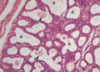

O lóbulo é formado de ________(Unidades secretoras tubulo alveolares/Ductos galactóforos). O lóbulo possui ______(Alvéolos/Pirâmides) que são compostos por células epiteliais secretoras de leite + celulas mioepiteliais.

Unidades secretoras tubulo alveolares - Alveolos

Composição dos alvéolos

Celulas epitelias secretoras de leite + células mioepiteliais

V ou F

O tecido conjuntivo que envolver os alvéolos é rico em plasmócitos e linfócitos, que contribui para secreção de imunglobulinas no leite

Verdadeiro

Identifique ‘‘A’’

Alveólos